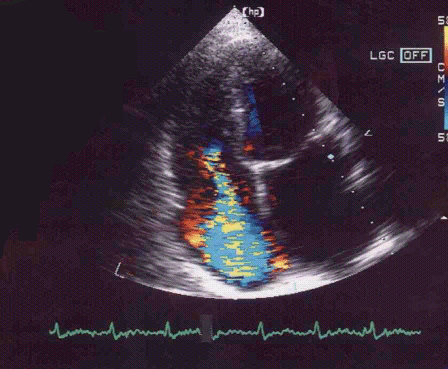

Kalp kapakları kanın bir yöne doğru geçmesine izin verirken ters yöne doğru kanın kaçışını engelleyen valvlerdir, kabaca evlerin su deposunda kullanılan 'check valv' (çek valv okunur) lere benzetebiliriz. Eğer kapağın yapısı bozulmuşsa kan geçmemesi gereken bölgeye doğru geçer, yani kalp kanı ileri, beyine doğru pompalamaya çalışırken bir miktarı da geriye doğru (istemeden) pompalanabilir. Bu durumda kalbin ileri doğru kan yeterli miktarda kan pompalamak için daha çok çalışması, daha çok kanı pompalaması gerekir, çünkü her kasıldığında pompaladığı kanın bir miktarı istenilen yere değil, geriye yani geldiği yere pompalanmaktadır. Kalp kapaklarındaki kaçakların şiddeti ve hastanın şikayetlerine göre hastalara ilaç daha sonra da gerekli olunca ameliyat veya diğer yöntemler uygulanabilir.Kalp kapaklarındaki daralmalar ise kanın yeterince atılamamasına neden olur, bu durumda darlık ciddi boyuta gelene kadar ilaçla tedavi edilebilir, ciddi boyuta geldiğinde ise balonla genişletilebilir veya ameliyatla kapak tamir edilir veya değiştirilir.